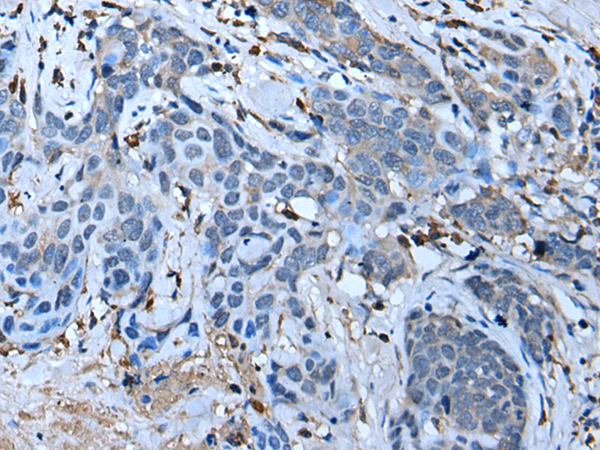

IHC positive control: |

Human thyroid cancer |